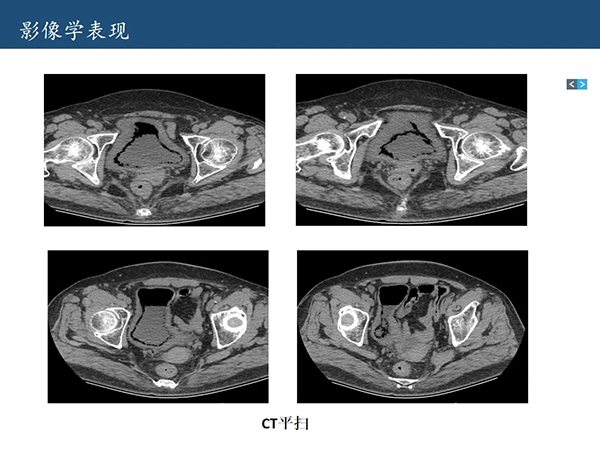

【病例讨论】放射科:气肿性膀胱炎